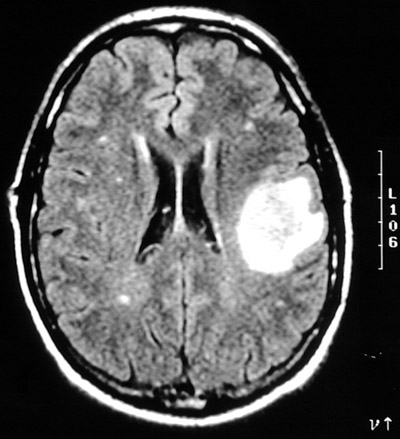

| These MRI scans in axial view, T2 weighted above and FLAIR below, demonstrate an enhancing solitary mass with minimal adjacent edema. This is a solitary metastasis from a pulmonary adenocarcinoma. In adults, metastases are more common than primary brain tumors. Typical primary sites include lung, breast, and kidney. |